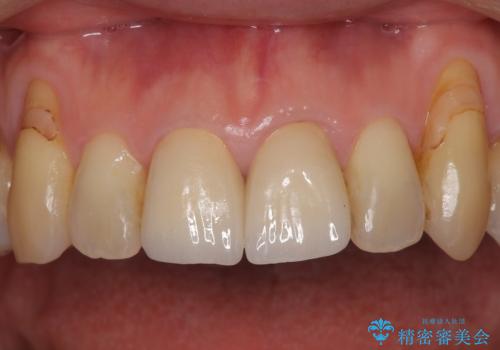

左右対称の2本の歯にセラミッククラウンを装着したことで、調和の取れた審美的な口元となりました。